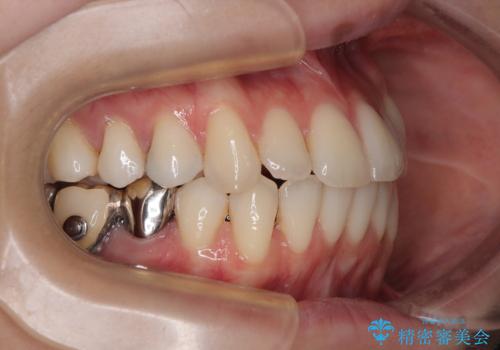

下顎臼歯部にブリッジが装着されており、移動不可のため、IPR(歯と歯の間を削る)と歯列全体を拡大させることで、歯並びを整えていくこととしました。

インビザライン特有の奥歯の噛みにくさが治療後半に発現しましたが、無事に終了させることができました。